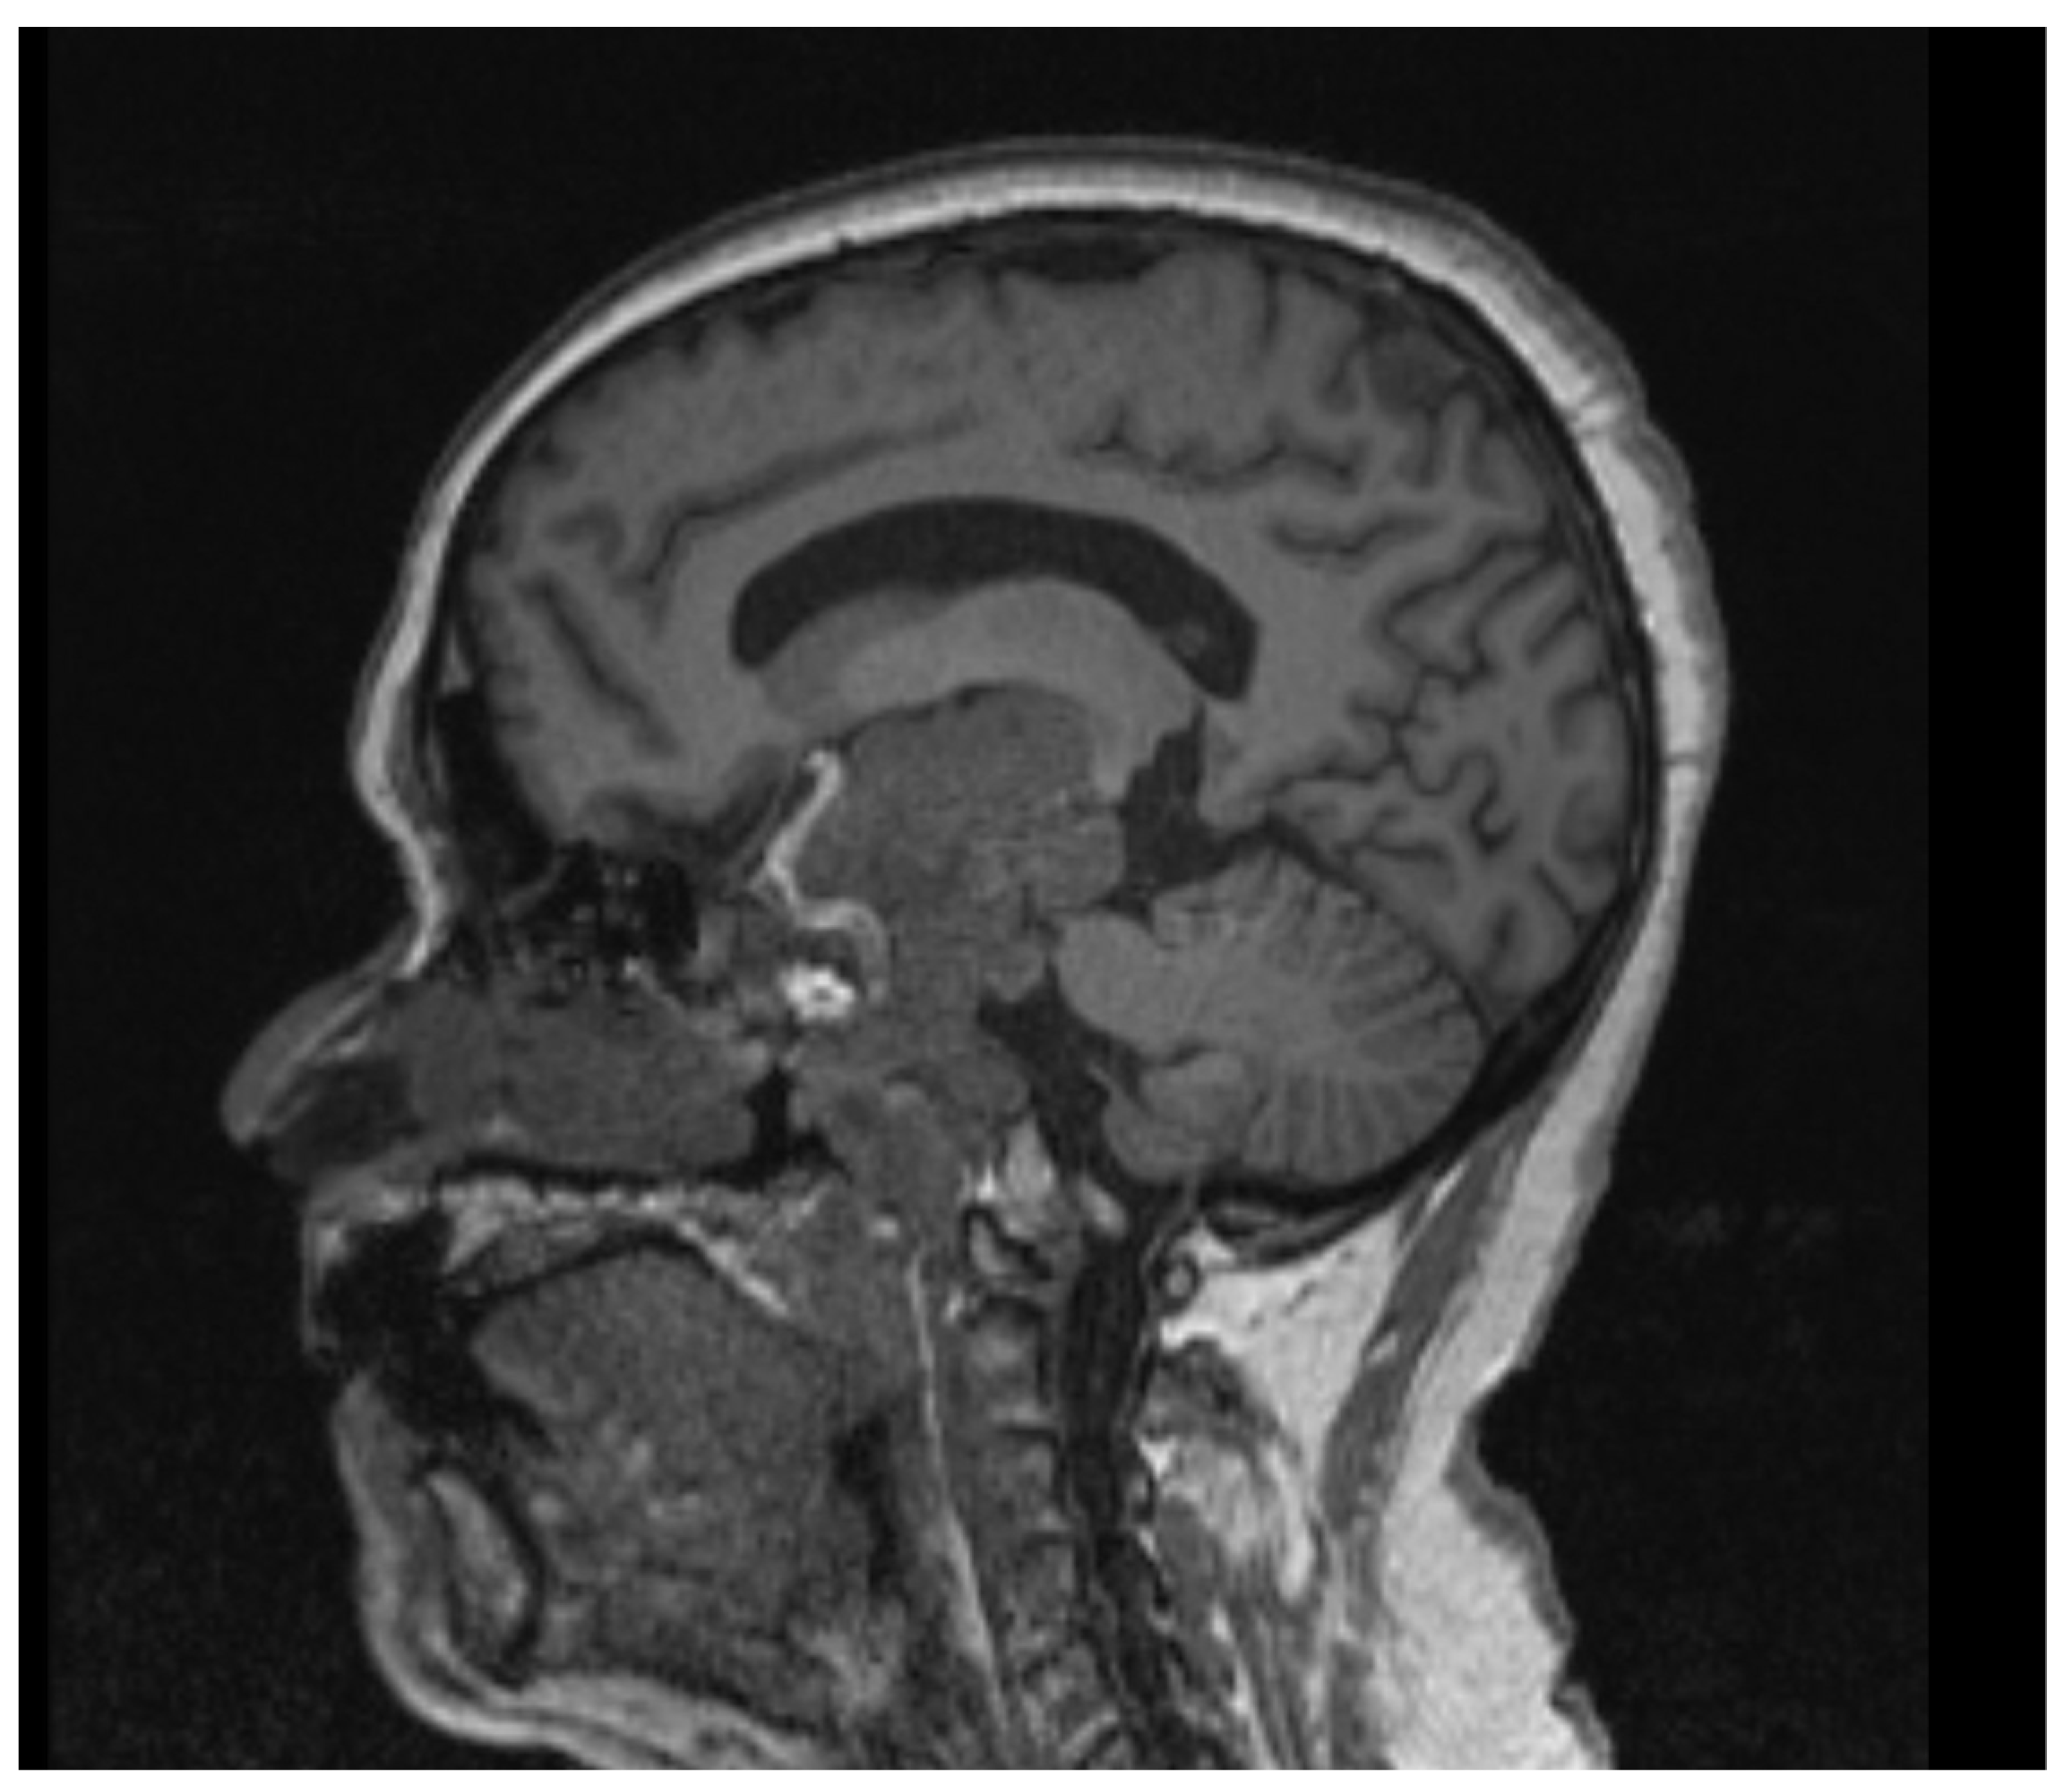

2.2. Case 2